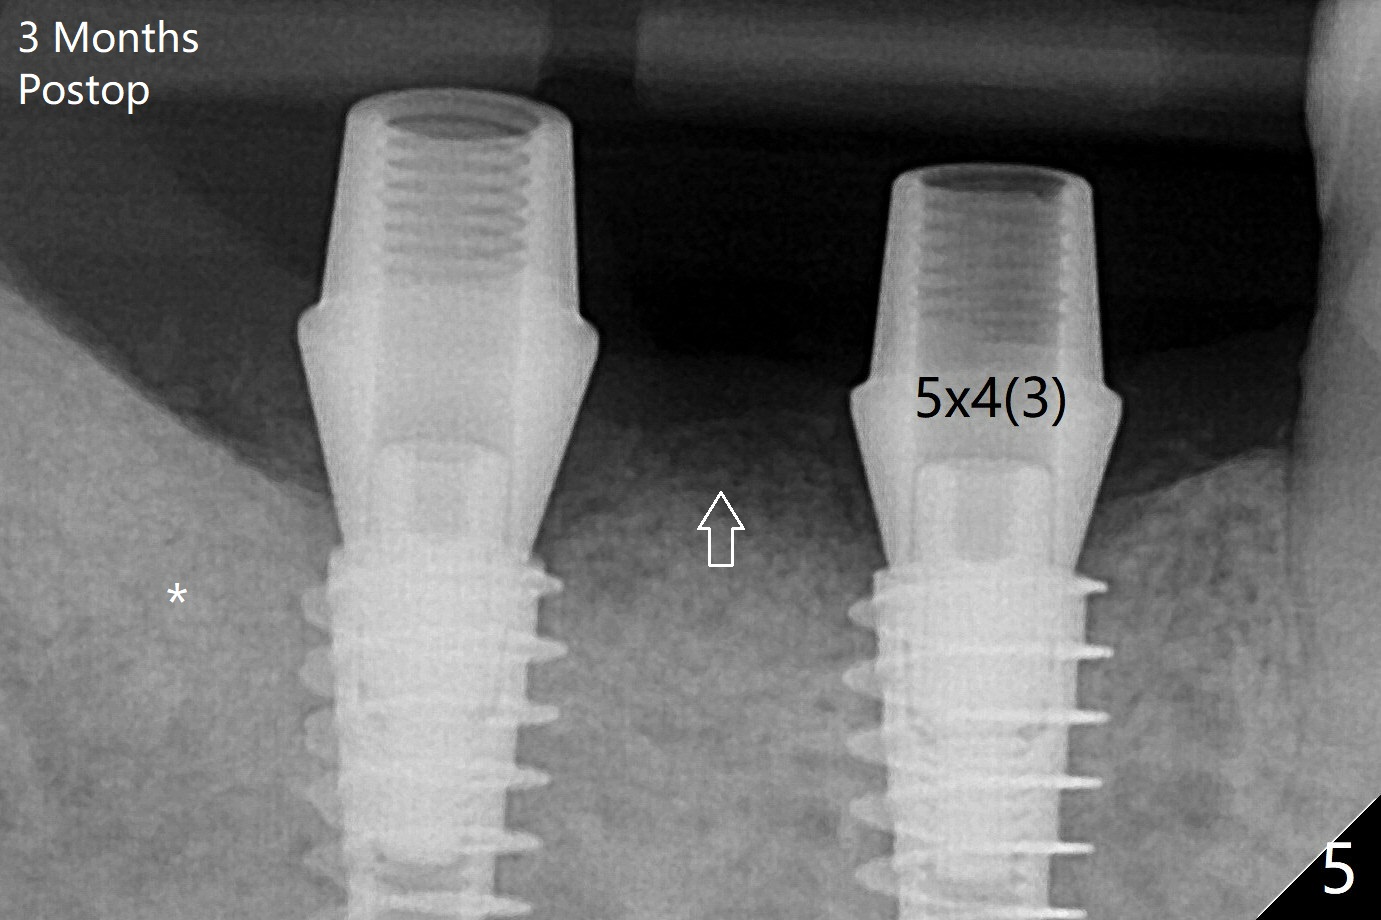

植入植体,6扭力低(因为植入近中窝),7高(6,7之间牙槽骨),所以安置愈合(6x5毫米)和修复(5.5x4(4)毫米)基台。原来导板设计把植体植入牙槽嵴(图三:白虚线)下1-2毫米,自动提高植体间牙槽嵴,接着把钻洞产生的骨粉放在后者上缘(*),由近中和远中基台固定。术后3个月7牙槽窝愈合(位点保存后10个月,图五:*),植体间牙槽嵴仍旧高(箭头),6放置修复基台,准备做临时牙冠。